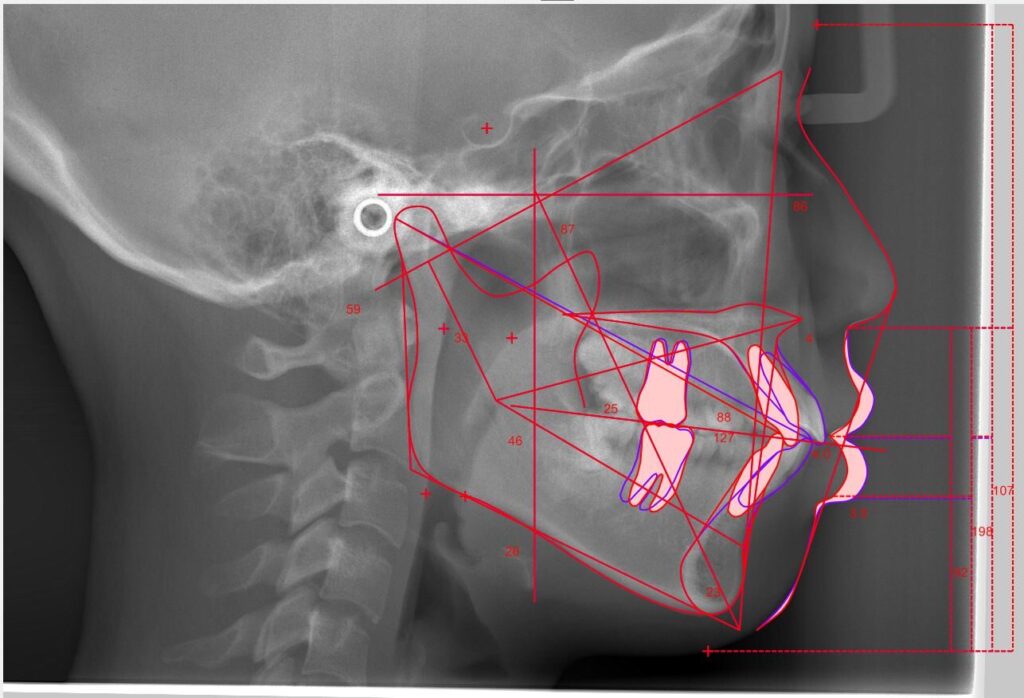

レントゲン・口腔内写真・3Dスキャンなどのデータをもとに、骨格・歯の傾き・噛み合わせを総合的に分析し、最適な治療方針を導き出します。